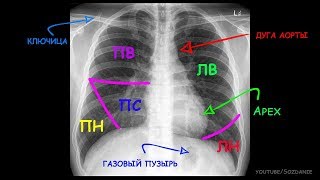

Как выглядит воспаление легких на снимке?

Из-за небольшого размера изображения и низкой четкости рентгеновского снимка грудной клетки это плохой диагностический инструмент и не всегда дает истинное изображение. Даже самому опытному специалисту будет сложно распознать тип пневмонии или точно оценить стадию заболевания.

Тем не менее, на вопрос, покажет ли флюорография пневмонию, ответ — да, чаще всего — да. Но в основном речь идет о выявлении самого факта заболевания, специфичность в этом типе исследования маловероятна, особенно когда болезнь находится в начальной стадии. Если снимок сделан на поздней стадии патологического процесса, можно различить очаговую и крупную пневмонию. На рисунке ниже показано, как выглядят эти типы пневмонии.

Опытный специалист, глядя на картинку, обращает внимание на следующие нюансы:

• Тонкие линейные ткани в большинстве случаев нечеткие, но это все же один из симптомов развития пневмонии.

• Наличие одной или нескольких световых точек, так называемых очаговые тени в проекции органа.

• Нерегулярное затемнение и яркость.

• Увеличение или утолщение легочных корней.

• Усиление легочного рисунка, образованного сосудами и указывающего на воспалительный процесс.

• Аномальное положение мышцы диафрагмы.

• Патологические отклонения в расположении органов средостения, их смещение, могут говорить о скоплении жидкости или воздушных масс в плевральных полостях.

Яркий пример — проникновение, выглядывающее сквозь тень сердца. В этом случае для уточнения диагноза необходимо сделать два проекционных рентгеновских снимка.